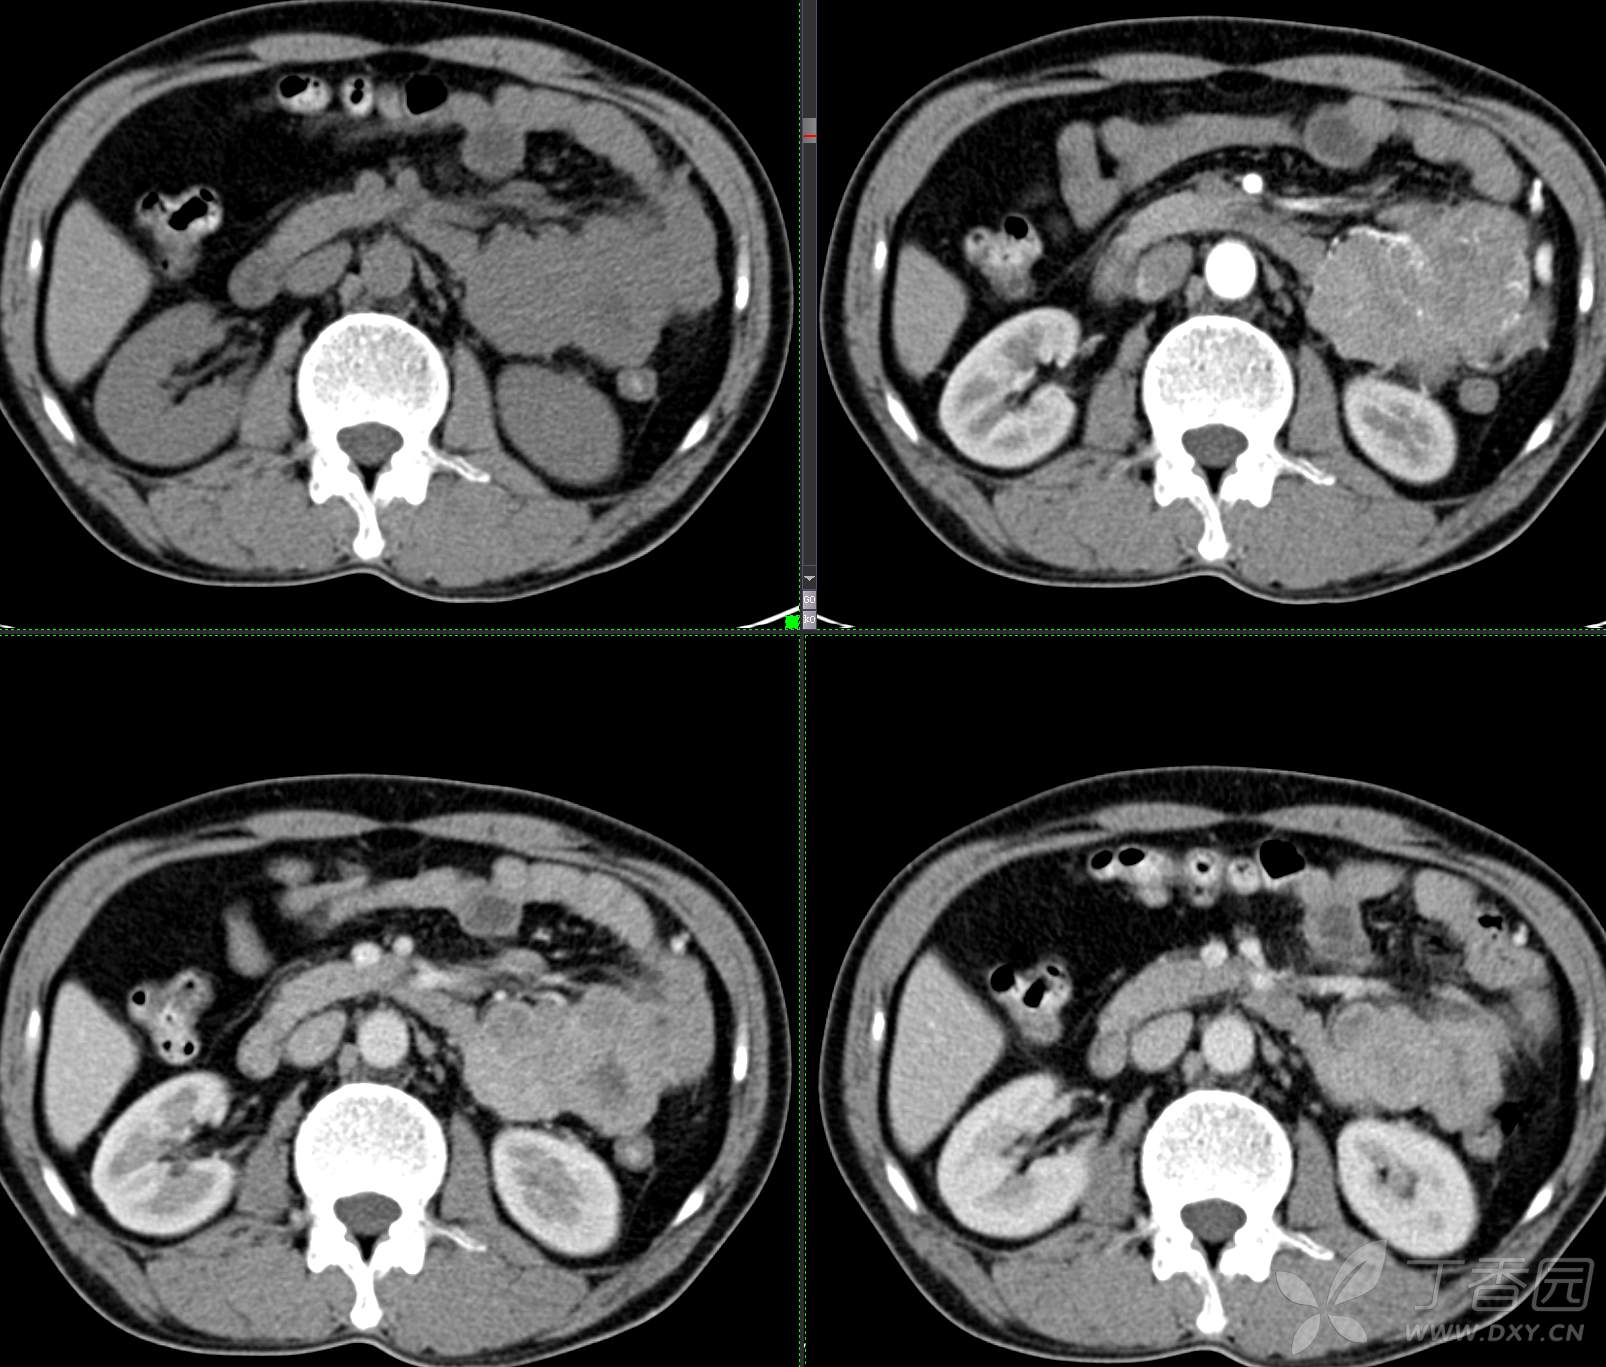

讨论:小肠病变,间质瘤?淋巴瘤?小肠腺癌?